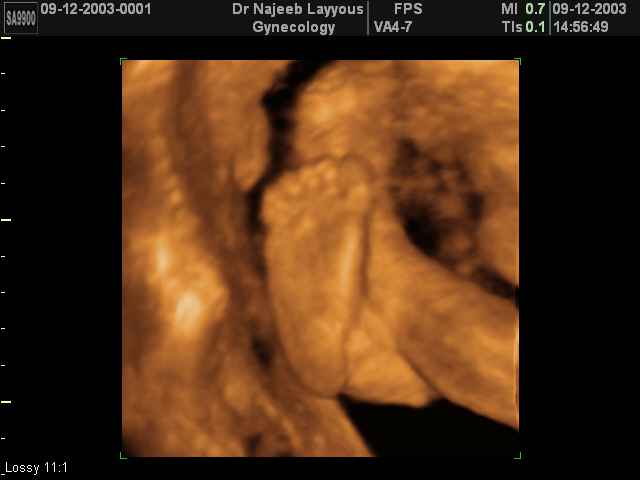

- صور لأطراف الجنين

صور لأعضاء الجنين بجهاز الموجات فوق صوتية ثلاثي الأبعاد | الدكتور نجيب ليوس